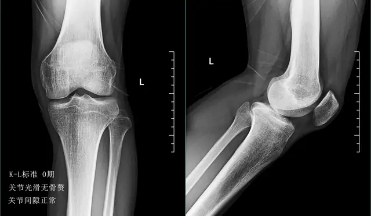

前面已经说到骨关节炎会导致骨赘的形成以及关节间隙的狭窄,所以我们依靠膝关节x片子来初步判断骨关节炎的病情,通常我们采用K_L分期判断病情。

0期的患者:也就是正常的患者,患者不会有任何的症状。

一期患者:患者的关节会开始有轻度的无罪行程,一般这个阶段的患者会有比较明显的上下楼梯的疼痛或者是不适,但是往往走平路反而正常,所以很多这个阶段的患者并没有得到很好的重视。在这个阶段,如果能开始注意保护我们的关节,减轻体重、减少对于关节的使用往往是可以逆转的,但是正是由于症状不是特别的明显,反而很多人忽视了这个病情。